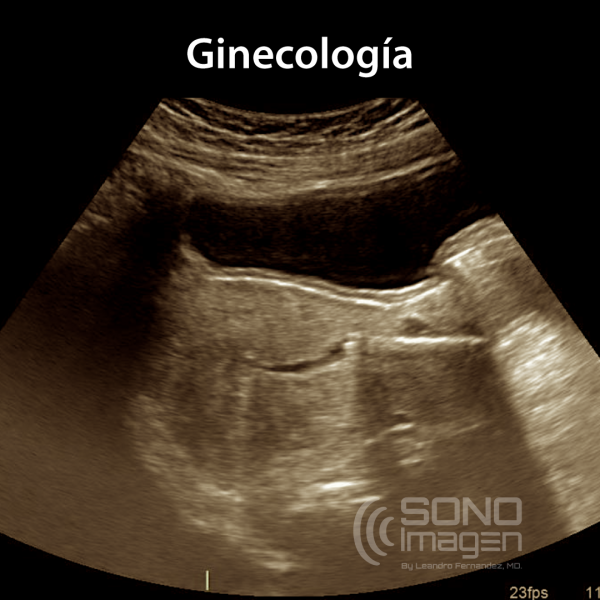

Ginecología

CURSO MASTERCLASS DE ULTRASONIDO EN GINECOLOGÍA

El curso Magistral online y streaming de ultrasonido ginecológico está diseñado para proporcionar una descripción total y completa de la técnica de examen en este importante campo de la ecografía. También se incluyen los fundamentos físicos, conceptos indispensables para la optimización de imágenes.